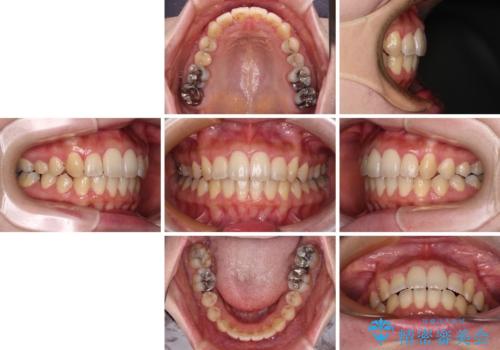

- 捻れた前歯が飛び出しており、口が閉じにくいとのことで来院された患者様です。

出っ歯というわけではないものの、前歯の捻転により口唇が押し出されている状態でした。

親知らずを抜去し、歯列全体を後方に移動させつつ、IPR(歯と歯の間を削る)でスペースを獲得し、インビザラインを用いて叢生を解消しながら前歯の突出を改善することとしました。

インビザラインは、患者様の協力無しには成立しない治療ですが、しっかりと装着時間を遵守してくださり、1年弱で治療を終えることができました。